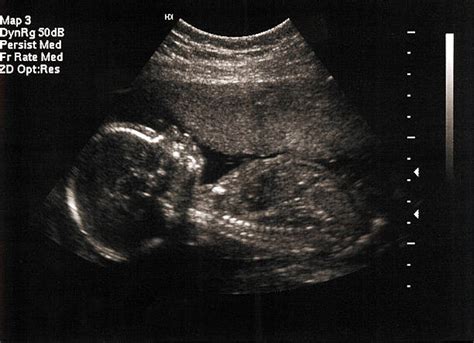

Zuzana si spočiatku nepripúšťala meškajúcu menštruáciu, pripisovala ju chorobe či vlastným želaniam. Keď však tehotenský test ukázal dve čiarky, jej radosť bola opatrná, vzhľadom na predchádzajúci potrat v šiestom týždni tehotenstva. Napriek tomu, že sa tešila z bijúceho srdiečka na ultrazvuku v siedmom týždni, jej nevoľnosti a hormonálne zmeny ju trápili.

V deviatom týždni prišla krutá diagnóza: plod sa nevyvíjal správne a jeho srdiečko bilo veľmi pomaly. Následné vyšetrenia potvrdili stratu. Zuzana podstúpila kyretáž, zákrok, ktorý bol pre ňu veľmi frustrujúcim zážitkom. Po návrate domov sa ocitla na psychickom dne, no snažila sa pred okolím tváriť, že je všetko v poriadku.